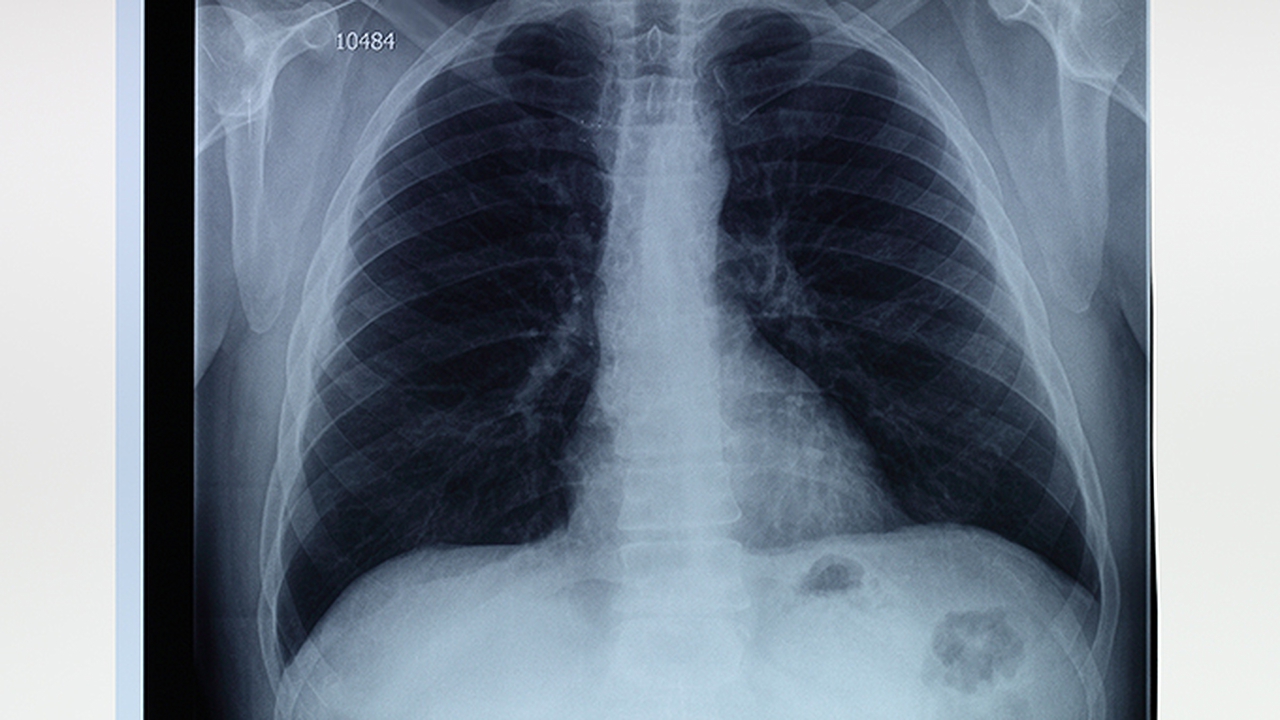

肺气肿是一种常见的慢性呼吸系统疾病,主要表现为肺泡壁破坏、肺组织弹性减退,导致呼吸困难、咳嗽等症状。中医认为肺气肿多与肺脾肾三脏功能失调有关,治疗上注重整体调理,通过中药、针灸、推拿等方法改善症状、延缓病情进展。